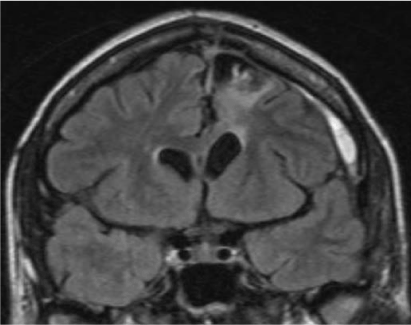

FRONTAL MRI